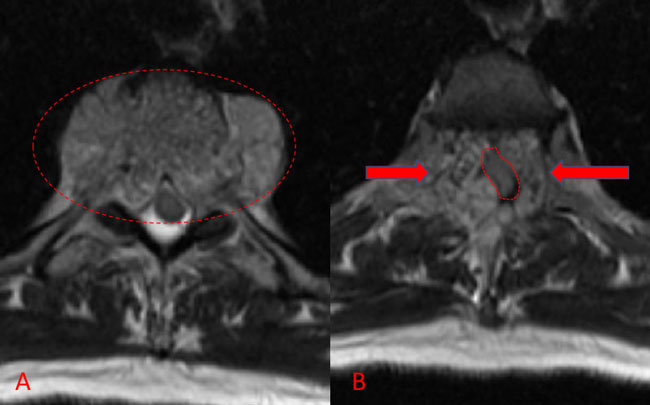

No spinal artery contributions were found to arise from this right T1-T3 pedicle. Superselective WADA testing was performed with Brevital injected through the microcatheter, which failed to elicit changes in the intraoperative monitoring, confirming safety to proceed with devascularization of this pedicle and tumor. This was performed with 100-300 micron particles achieving an excellent devascularization (Figure 3. A, B).

Figure 3. A and B) demonstrates selective PVA embolization with complete devascularization of the tumor on completed embolization.

The patient underwent a safe and successful posterior decompression with corpectomy and instrumented fusion with minimal blood loss and discharged home with reversal of neurologic deficits and resolution of symptoms.